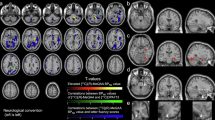

Tregellas JR, Olincy A, Johnson L, Tanabe J, Shatti S, Martin LF et al (2010). Functional magnetic resonance imaging of effects of a nicotinic agonist in schizophrenia. Neuropsychopharmacology 35: 938–942.

Tregellas JR, Tanabe J, Rojas DC, Shatti S, Olincy A, Johnson L et al (2011). Effects of an alpha 7-nicotinic agonist on default network activity in schizophrenia. Biol Psychiatry 69: 7–11.